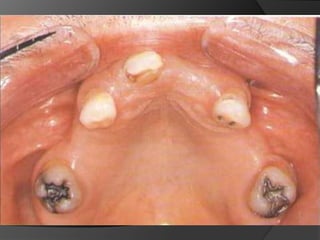

CORONAS DE RECUBRIMIENTO PARCIAL - ¾ SUPERIORESRestauración conservadoraPermiten evaluar con exactitud asentamiento de márgenesFácil escape del material cementanteLa pared no tallada sirve como guía de fabricación de contornosPermite pruebas de vitalidad pulparEstética en veremos

CORONAS DE RECUBRIMIENTO PARCIAL - ¾ SUPERIORESIndicaciones:Superficie vestibular intacta (Esmalte-Dentina)Porcentaje de caries mínimoDiente de longitud suficienteBuena higieneNecesidad estética baja o moderada